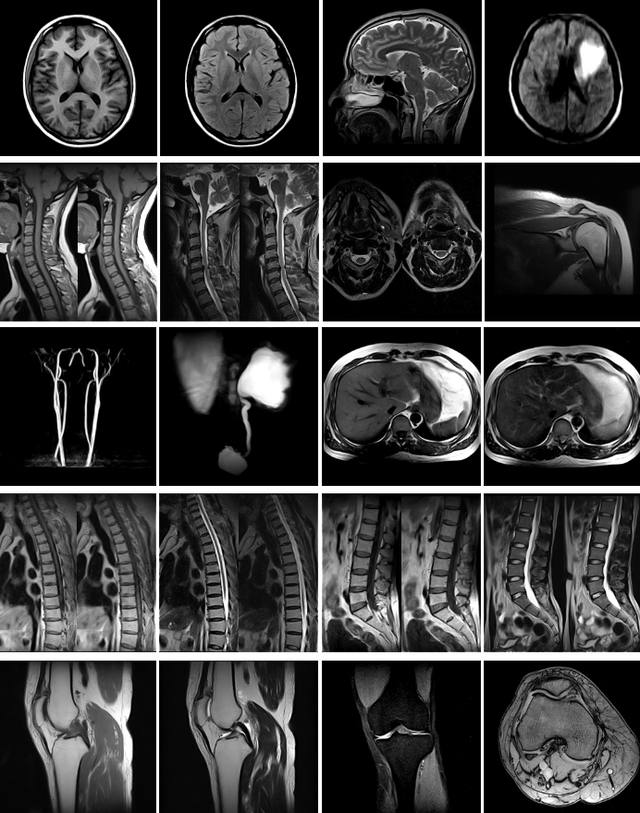

Радіочастотні котушки для дослідження голови, спини / тіла великого, середнього і малого розміру, гнучкі котушки для спини / тіла великого, середнього і малого розміру, шийного відділу хребта, молочної залози, плечового, лучезапястного, гомілковостопного і колінного суглобів.